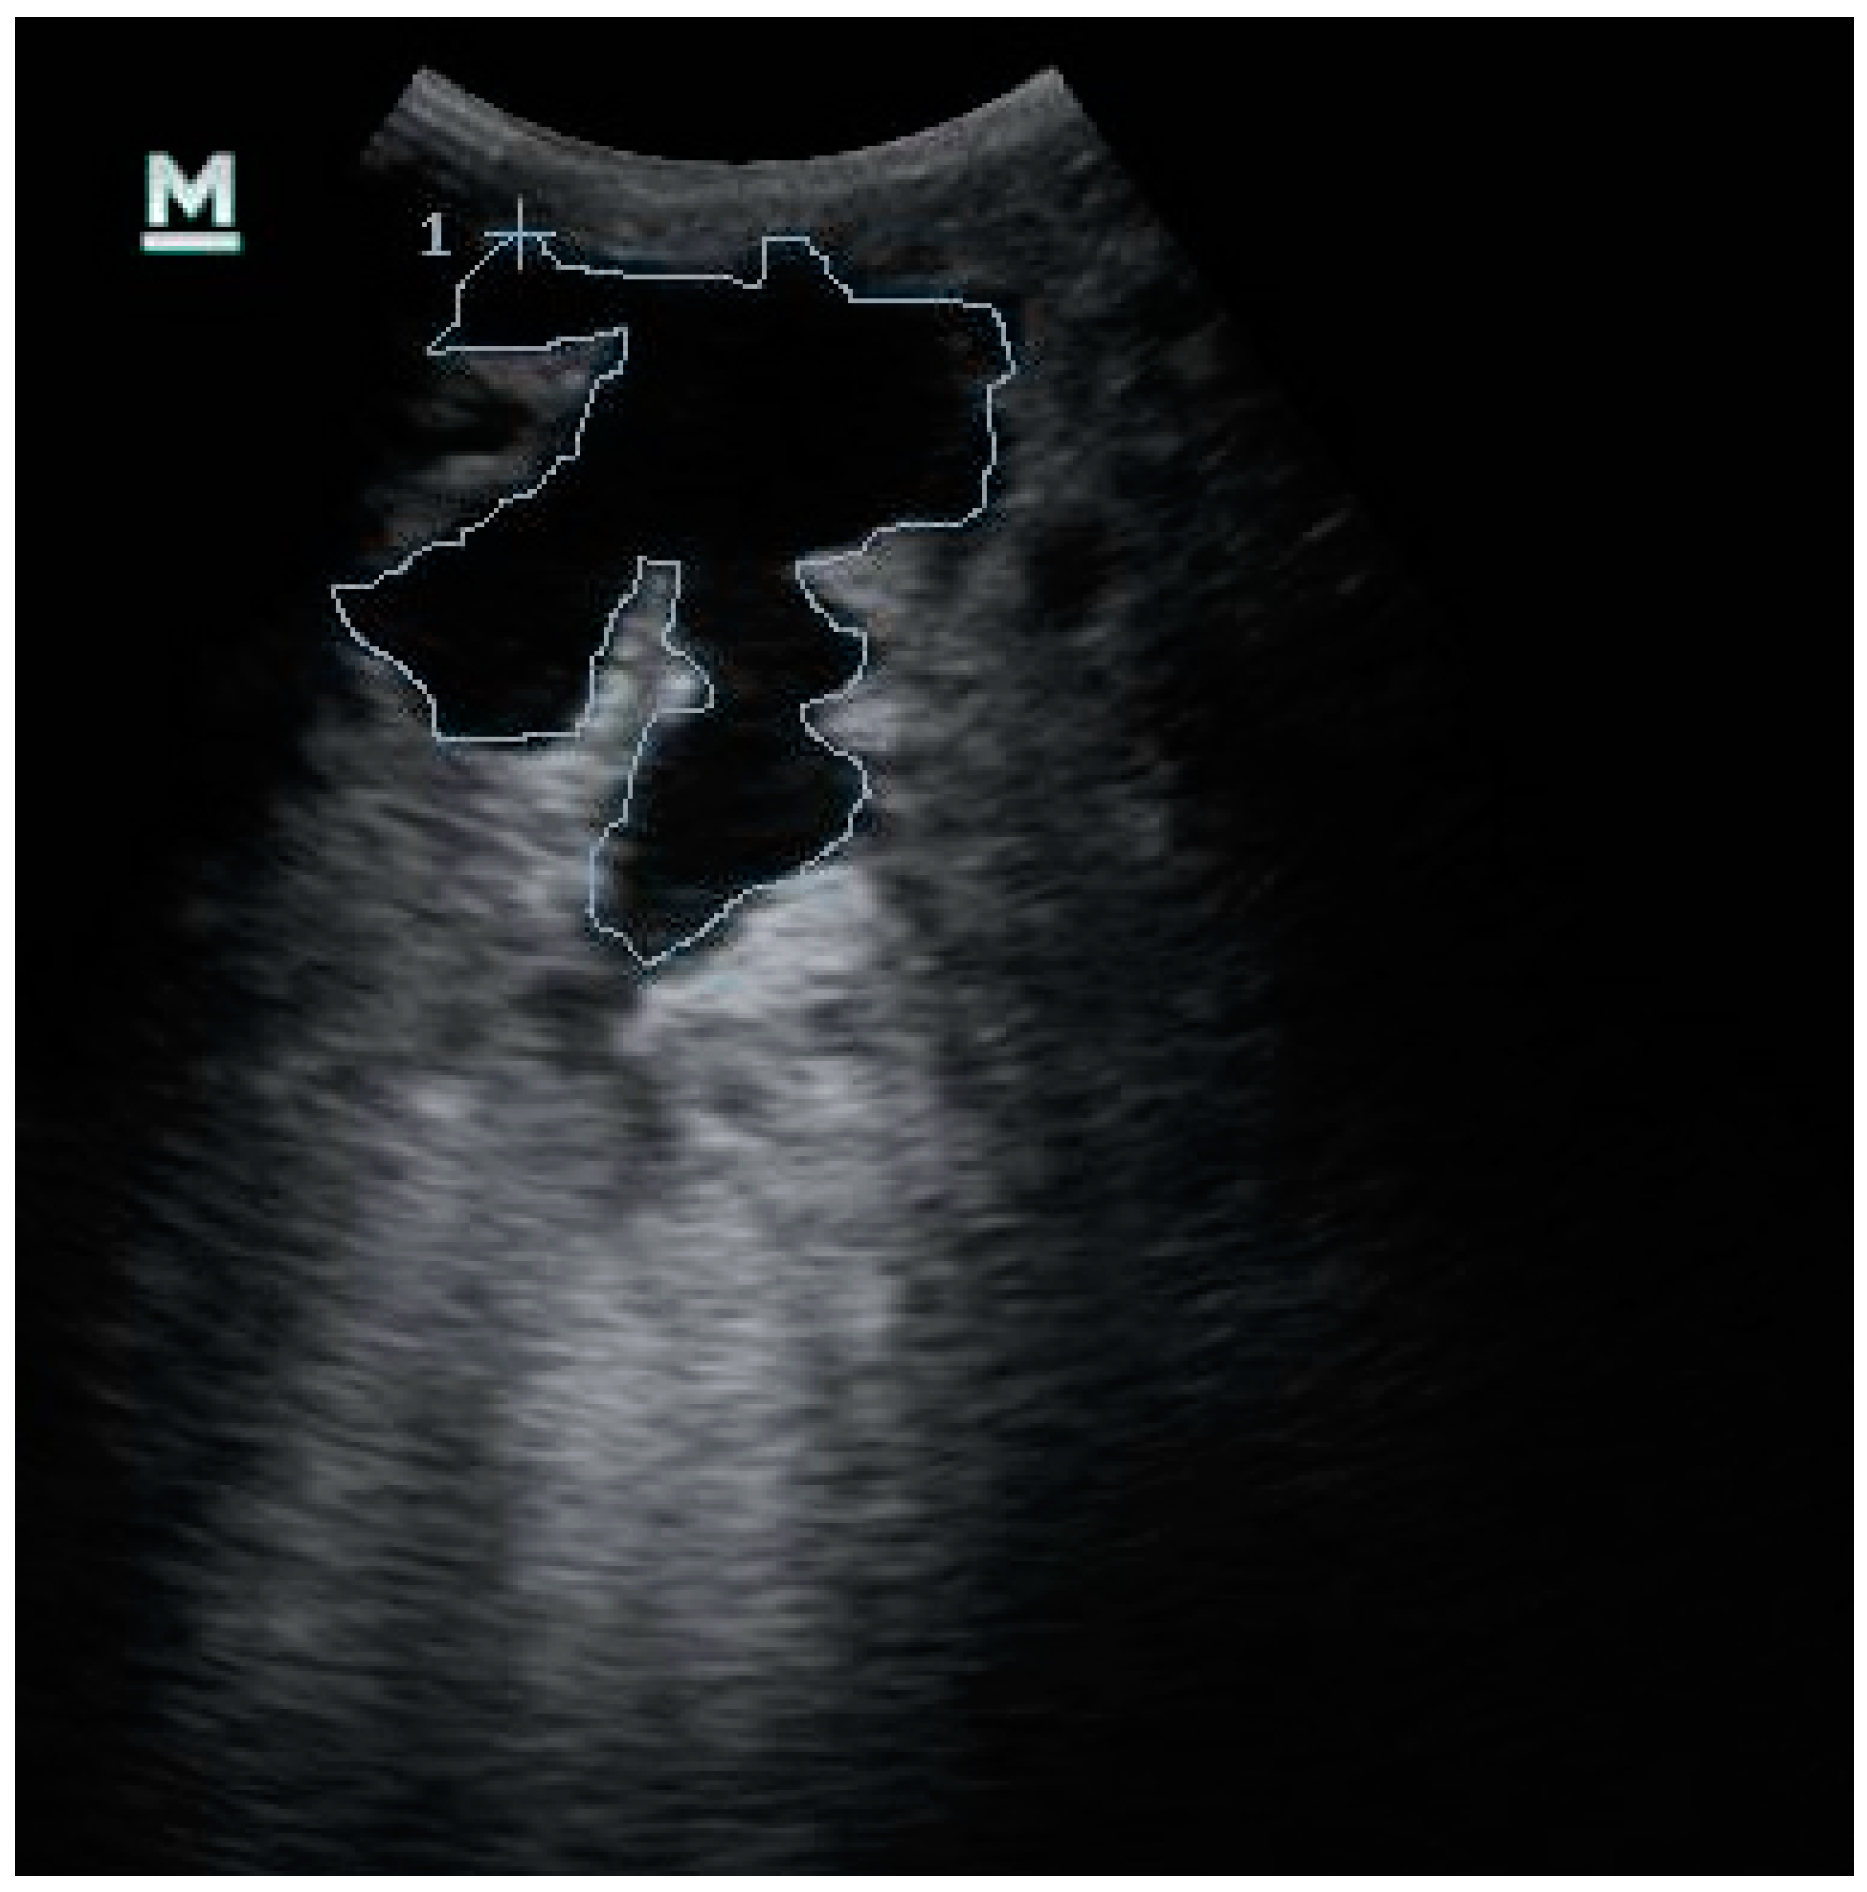

2.3. Ultrasonographic Examination of the Udder

2.4. Ultrasonographic Images Evaluation